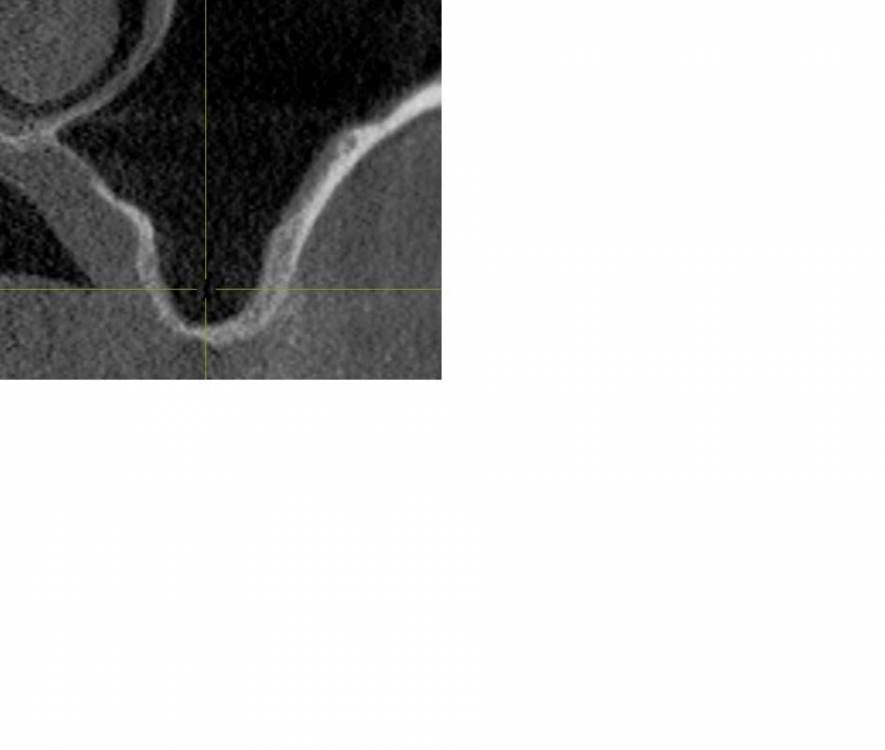

kamranchick Опубликовано 5 августа, 2021 Поделиться Опубликовано 5 августа, 2021 Приветствую, первый раз сталкиваюсь с подобной ситуаций стандартная ситуация, ОСЛ с использованием чистого апатос кортикал, ожидание 5 месяцев,заживление без осложнений сегодня начинаю сверление, и один сплошной фиброз какой прогноз коллеги? стоит ждать чуда? прилагаю снимки Ссылка на комментарий

kamranchick Опубликовано 14 августа, 2021 Автор Поделиться Опубликовано 14 августа, 2021 интересно причины, почему такое получилось, плотная паковка, проверенный костный заменитель, окно перекрыто мембраной Ссылка на комментарий

Irouil Опубликовано 14 августа, 2021 Поделиться Опубликовано 14 августа, 2021 А как именно себя фиброз проявил? может быть отслойка по каудальной стенке получилась не «чистой» - по КТ «после» только там есть намёк на неравномерный контакт графта и костной поверхности Ссылка на комментарий